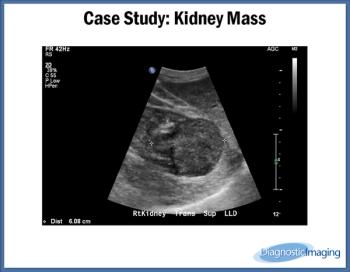

Kidney Mass

Case History: 90-year-old male had a mass on his right kidney seen on previous ultrasound that was being followed for growth.